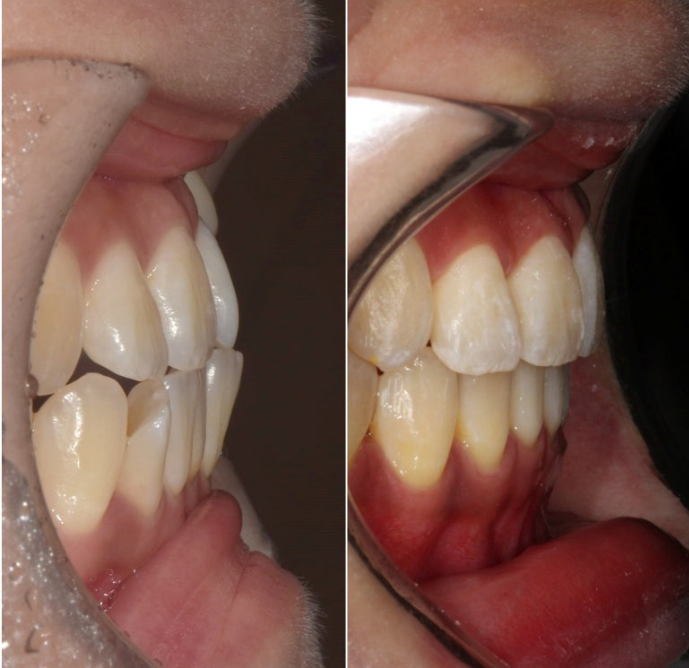

23.09

왼쪽 송곳니 하나가 완전히 배열에서 벗어나 있습니다.

덧니가 있으면 덧니쪽으로 중심선이 쏠리기 마련입니다.

위 앞니 중심선이 덧니쪽으로 틀어져 있는 것이 보입니다.

송곳니가 덧니가 제자리로 들어올 공간이 단 1mm도 없습니다.

심한 덧니입니다.

앞니는 윗니가 아랫니를 덮지 못하고 거꾸로 물리는 반대교합과 절단교합이 보입니다.

23.09~25.03

초진 3mm의 중심선 불일치가 해결되었습니다.

윗니가 아랫니를 덮는 양이 안정적입니다.

잘 내려와준 덧니입니다.

앞니가 거꾸로 물리던 부분도 정상교합을 찾았습니다